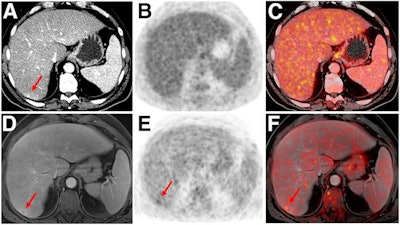

PET/CT tends to be the gold standard for oncologic imaging because of its sensitivity, even though PET/MRI has higher soft-tissue contrast and lower radiation exposure, the group noted. But there are few data on PET/MRI's performance for oncologic imaging.

- PET/MRI identified additional, pertinent clinical findings in 26.3% of the exams compared with PET/CT.

- Of these additional PET/MRI findings, 5.3% were malignant, which led to a change in cancer staging in 2.9%.

- PET/MRI clarified indeterminate PET/CT findings in 11.1% of exams.